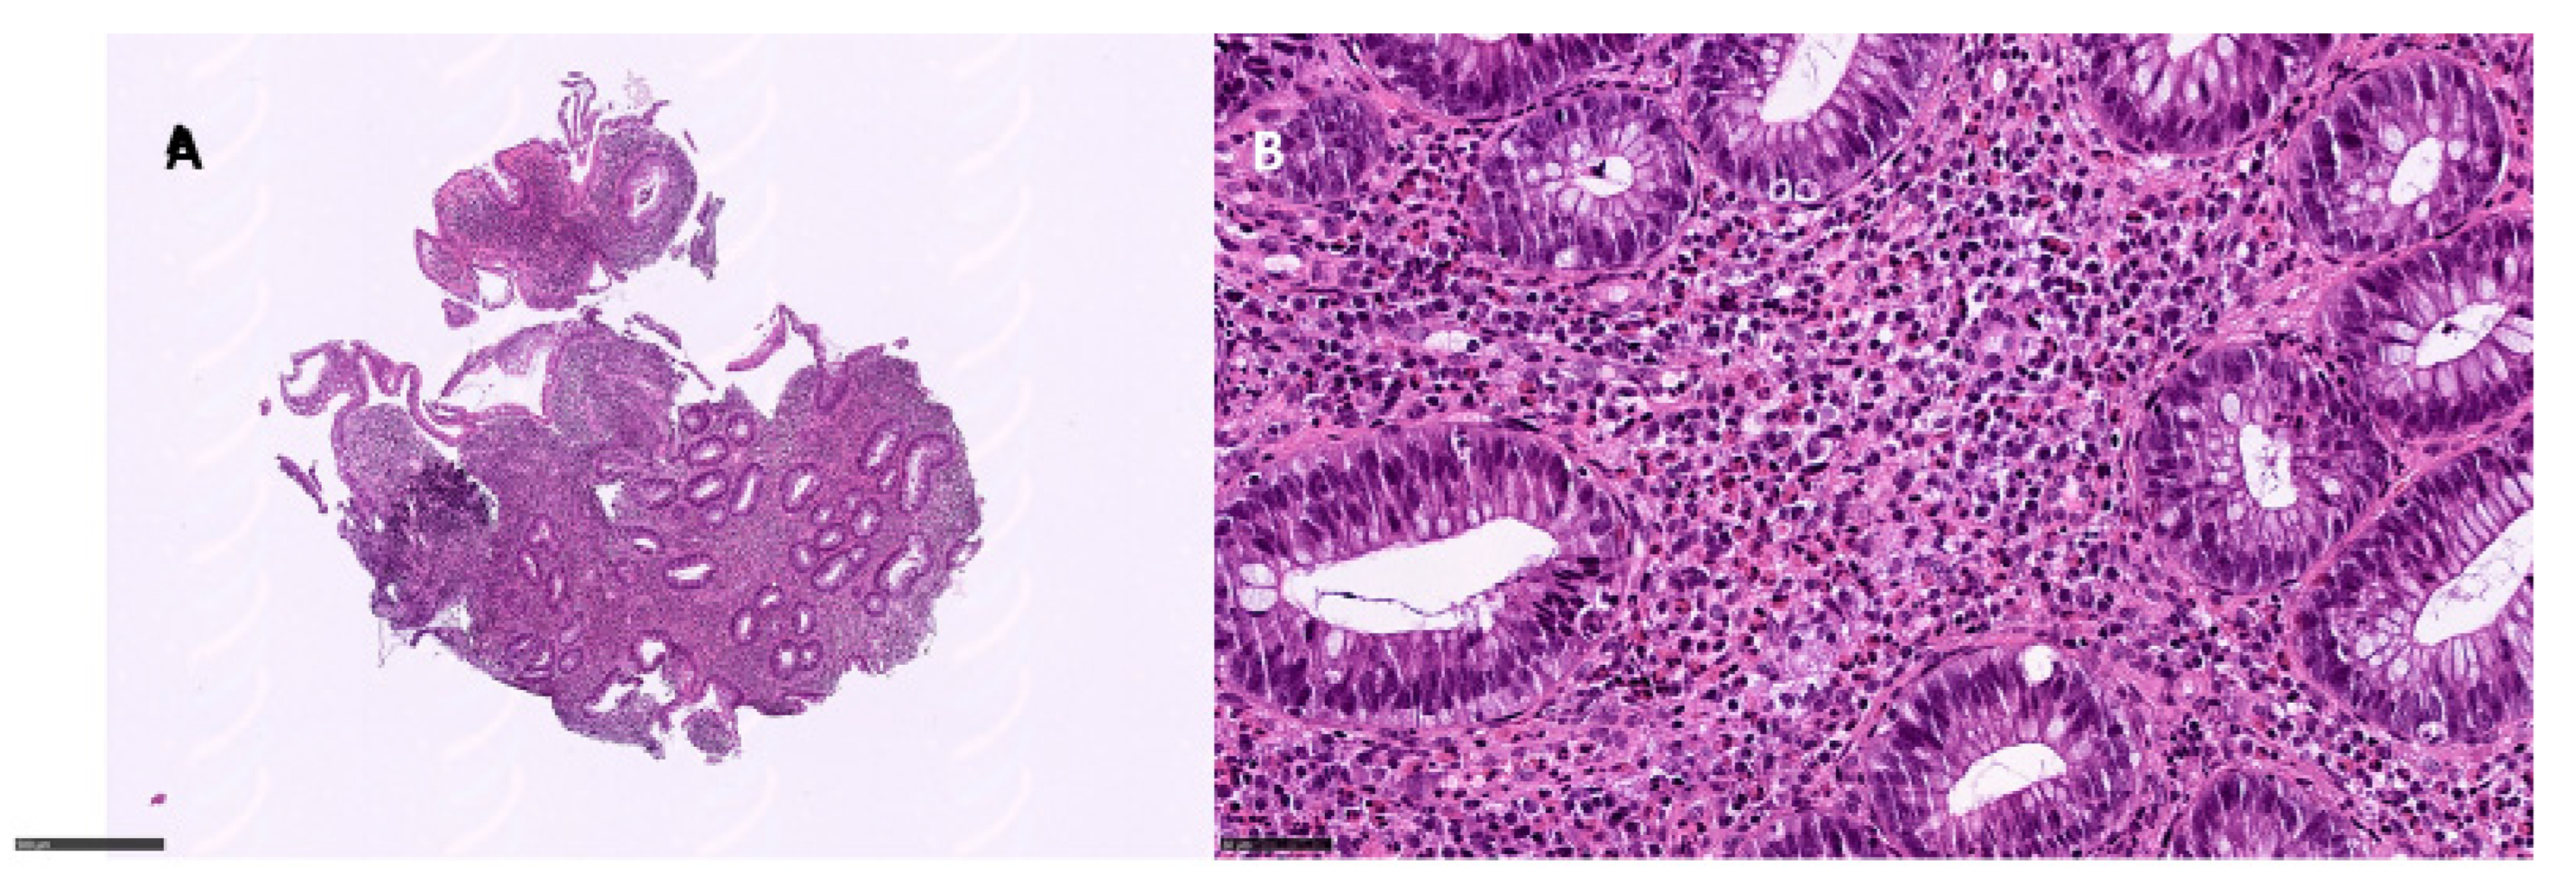

Of the 21 patients, 8 underwent ileo-pancolonoscopy with whole mucosal sampling. Among these, apoptotic combined with ischemic and eosinophilic pattern colitis was observed in two patients, an apoptotic pattern was observed in two patients (Figure 2), apoptotic combined with an IBD pattern was observed in one patient, and apoptotic combined with an ischemic pattern was observed in another patient (Table 3). Eosinophilic pattern colitis was documented in one patient (Figure 3). One patient showed only active colitis. In two patients, the villous blunting of ileal mucosa was documented. CMV was found in two patients.

Figure 3.

Eosinophilic pattern colitis: (A) left colon, 6×, showing a dense inflammatory infiltrate in the lamina propria with middle glandular distortion; (B) eosinophils > 60/HPF in the lamina propria (hematoxylin and eosin).

Four patients underwent endoscopic intestinal polypectomy, due to endoscopic normal examen. An eosinophilic pattern was documented in three patients, while an apoptotic pattern was documented in one patient.